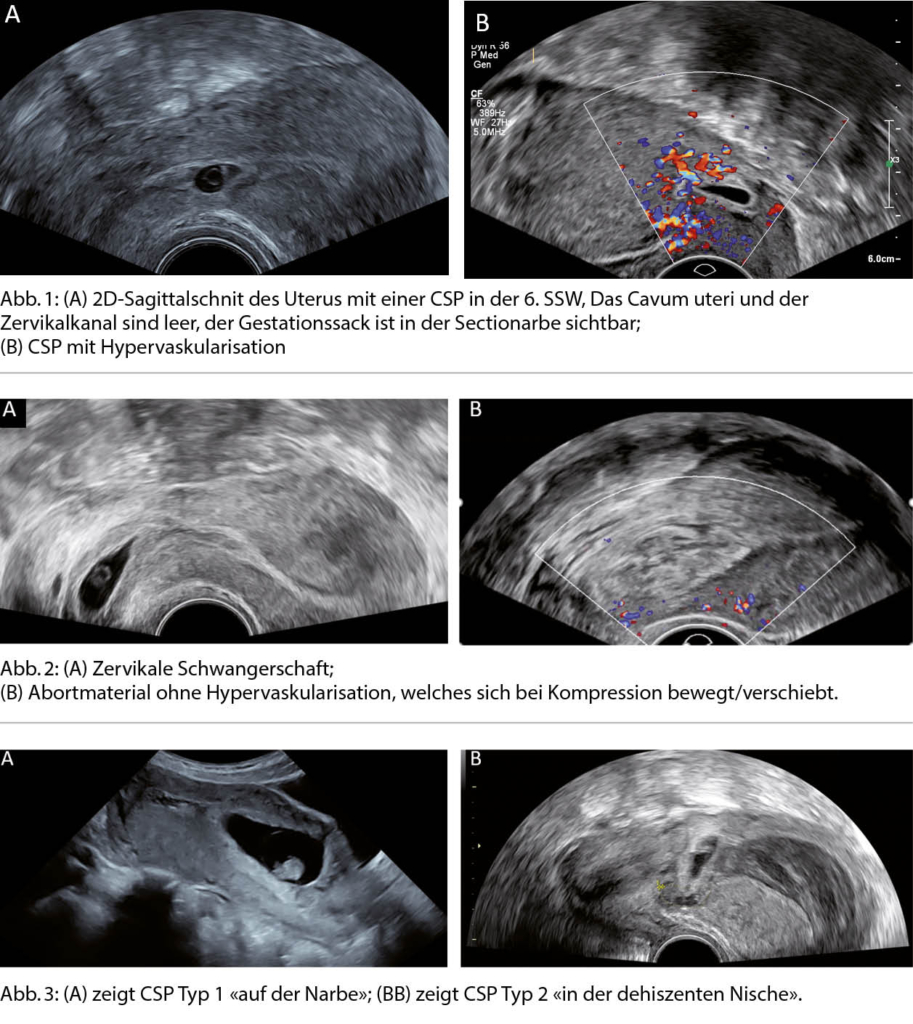

In der Schweiz gebären 1/3 der Schwangeren mittels Kaiserschnitt, das waren im Jahr 2017 knapp 28000 Kaiserschnitte. Eine seltene, gefährliche Spätkomplikation sind Kaiserschnittnarbenschwangerschaften (CSP). Die echte Inzidenz von CSP ist unbekannt, Schätzungen gehen von 1:1800 bis 1:2500 Schwangerschaften nach Kaiserschnitt aus. Im klinischen Alltag bemerken wir eine Zunahme an CSPs und Plazentationsstörungen (PAS), einer häufigen Folge der CSP. Bei der CSP implantiert sich der Fruchtsack in der Narbe, die durch den Kaiserschnitt entstanden ist (Abb. 1). CSPs sind eine ernste und potenziell lebensgefährliche klinische Entität mit einer Komplikationsrate von ca. 40%, hauptsächlich als Folge von verpassten Diagnosen oder möglicherweise unangemessenen Behandlungen, die schwere Blutungen verursachen (1). Bis heute gibt es noch kein standardisiertes Managementprotokoll für CSP.

Die transvaginale Sonographie in der Frühschwangerschaft ist Mittel der Wahl zur Diagnose der CSP. Sie kann bereits in der 5.-7. SSW anhand der folgenden sonographischen Merkmale gestellt werden (Abb.1) (2, 3):

- Leeres Cavum uteri

- Leerer Zervikalkanal

- Plazenta oder Gestationssack in der ehemaligen Uterotomie

- Dünnes Myometrium zwischen Blase und Gestationssack (1-3 mm)

- Starke Vaskularisation im Bereich der Narbe/Plazenta

Als wichtigste Differentialdiagnosen sind eine zervikale Schwangerschaft und ein Abortus incipiens/incompletus (keine Hypervaskularisation, verschieblich/beweglich) zu berücksichtigen (Abb. 2A und 2B).